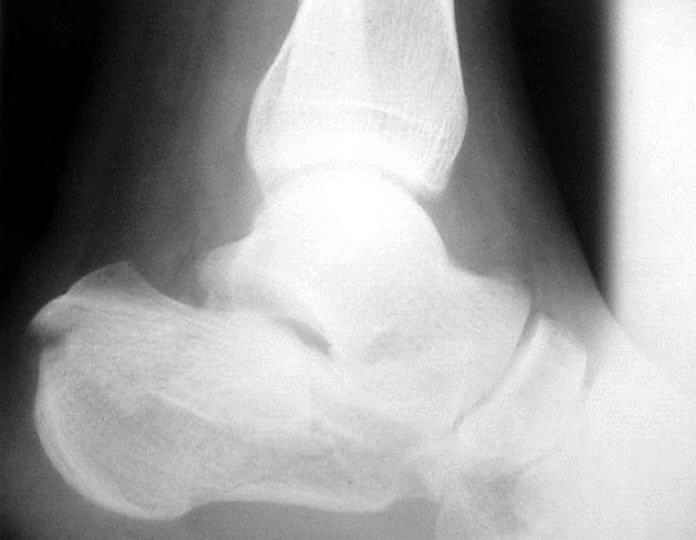

Пациент 36 лет поступил к нам с травмой стоп после падени яс высоты 6 м. С одной стороны подвывих в суставе Лисфранка, с другой переломпяточной кости (см. приложение).

У нас при обсуждении мнения разошлись. Каков тут оптимальный план лечения? Если оперировать,удастся ли закрыто достичь восстановления конгруэнтности таранно-пяточного сустава? Удастся ли зафиксировать результат открытого вправления стандартной пяточной фигурной пластиной, или лучше фиксировать отдельными треть-трубчатыми пластинами?Заранее спасибо.

Стандартные проекции не дают полной информации о тяжести повреждения таранно-пяточного сустава.

Решая вопрос о возможности реконструкции необходимо выполнение компьютерной томографии, которая даст ясную картину тяжести повреждения сустава (два фрагмента или несколько) и соответственно спланировать реконструкцию.

Закрытая репозиция маловероятно восстановит конгруэтность суставной поверхности , лигаментотаксис эффективен при 1 и 2 типах переломов пяточной кости( Essex Lopresti классиф)

Данный перелом можно классифицировать как "языкообразный" (по Essex-Lopresti), но имеется еще раздробление переднего отдела пяточной кости.

Как метод выбора, по мнению нашей клиники, является закрытая аксиальная репозиция аксиальная фиксация "языкообразного" фрагмента винтом Шанца под контролем ЭОПа. Технически это возможно в сроки до 10 дней, важно правильно